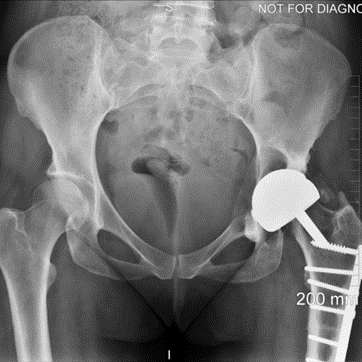

This case involves a 67-year-old gentleman who faced a series of complications due to hip trauma he had experienced over 50 years ago. After his primary and revision surgeries, and subsequent three hip replacements, he was left with a failing hip implant. His most recent hip replacement lasted 13 years before massive circumferential acetabular osteolysis caused the cup to loosen. Imaging revealed anterior and medial wall deficiencies, while the posterior column remained intact. The patient had a metal-on-polyethylene (MoP) bearing, which over time led to the wear of the polyethylene liner, triggering an inflammatory reaction and bone loss due to polyethylene debris.

The surgical plan required a custom 3D-printed acetabular cup, designed specifically for the patient's anatomy. The implant was designed with three flanges for optimal fixation. The surgery involved a posterior approach, with meticulous bone preparation to minimize further bone loss and ensure the custom implant fit securely.

This case represents ALTR with MoP. ALTR was characterized by massive osteolysis of the pelvic bone, which was most likely caused by polyethylene wear debris. This case underscores the complexity of revision hip surgeries and highlights the value of custom 3D-printed implants for achieving secure fixation and improving patient outcomes despite significant bone loss. Update at 7 years post operative is that the patient has excellent hip function and more can be seen in this paper: